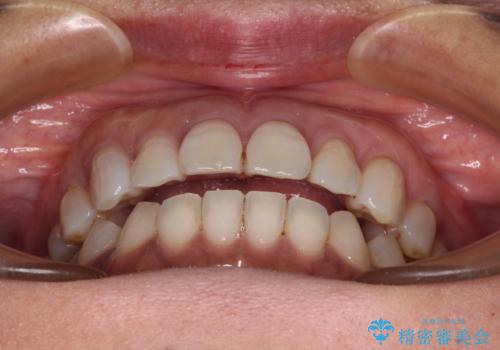

極端な上下前歯の開咬を改善 オープンバイトのインビザライン矯正

- 上下前歯の隙間を気にして来院された患者様です。

開咬の治療は、前歯を閉じるように動かすとともに、上下臼歯を圧下(骨内にめり込ませる)させることで進めて行きます。

治療前に、いくらインビザライン矯正がオープンバイトを得意としているとは言え、さすがに限界があるだろうと思っておりましたが、前歯でレタスが噛めるまで改善することができました。

顔の印象も大きく変わり、患者様には大変満足していただきました。